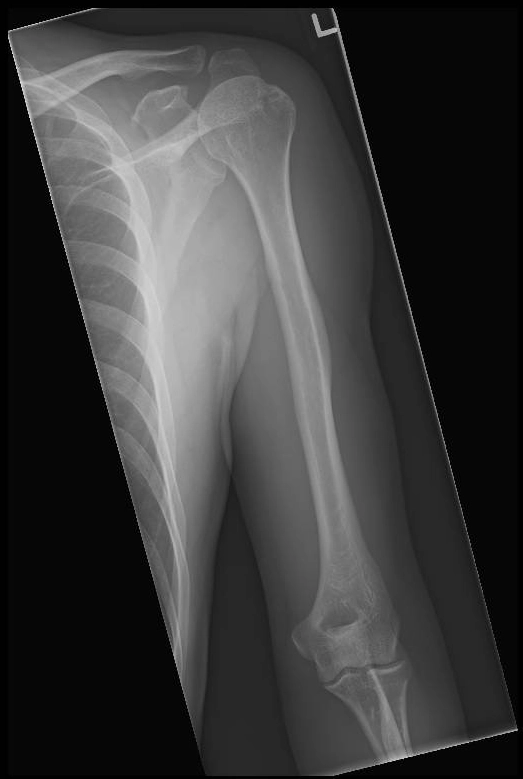

X Quang xương cánh tay

16/03/2026